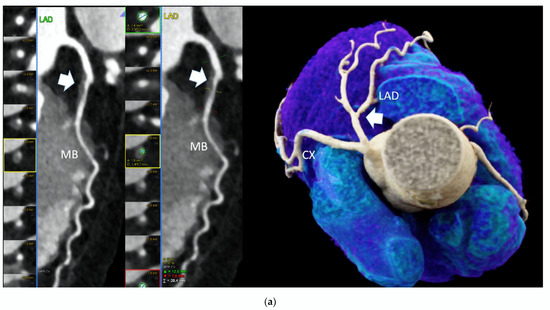

Out of those 103 with CAD and CACS 0, 52 (50.4%) had at least one HRP per patient (Figure 1).

Figure 1.

High-risk plaque (HRP) in a patient with CACS 0, a 70 years-old-male patient with ST-depression on ECG-treadmill stress test in V3-6. CT showed 37% diameters stenosis and a high-risk plaque (LAP 44 HU, positive remodeling) (white arrow) in the proximal left anterior descending artery (LAD), which were not detected by CACS (b). Diagnosis of non-obstructive CAD by CTA. Distal segment with deep myocardial bridging (MB), explaining stress test findings. (a) CTA (left: cMPR and right: 3-DVRT, spider view). LAD = left anterior descending. CX = circumflex artery.